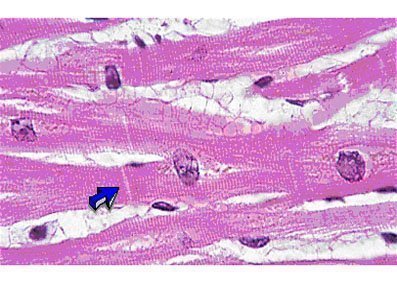

Músculo cardiaco

Constituido por células alargadas, formando columnas que se anastomosan irregularmente. Estas células también presentan estriaciones transversales, pero pueden distinguirse fácilmente de las fibras musculares esqueléticas por el hecho de poseer solo uno o dos núcleos centrales. La dirección de las células cardíacas es muy irregular y frecuentemente se pueden encontrar con varias orientaciones, en la misma área de una preparación microscópica, formando haces o columnas.

Esas columnas están revestidas por una fina vaina de tejido conjuntivo, equivalente al endomisio del músculo esquelético. Hay abundante red de capilares sanguíneos entre las células siguiendo una dirección longitudinal a éstas.

La célula muscular cardiaca es muy semejante a la fibra muscular esquelética , aunque posee más sarcoplasma, mitocondrias y glucógeno. También llama la atención el hecho de que en los músculos cardiacos, los filamentos ocupen casi la totalidad de la célula y no se agrupen en haces de miofibrillas.

Una característica específica del músculo cardiaco es la presencia de líneas transversales intensamente coloreables que aparecen a intervalos regulares.